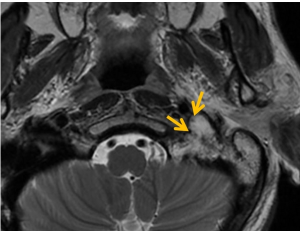

4、MRI 在診斷椎旁間腫塊是否為副神經節瘤方面有一定價值。副神經節瘤顯示為非同質性腫塊,內有可流動物質,後一種特徵是因為血管豐富,血流速度快。